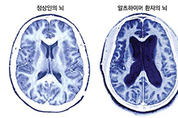

치매 환자가 체중이 급격히 줄어들 경우 사망 위험이 크게 증가한다는 연구 결과가 나왔다. 고려대학교 구로병원 가정의학과 남가은 교수와 서울성모병원 가정의학과 허연 교수, 숭실대학교 정보통계보험수리학과 한경도 교수 연구팀은 국민건강보험공단 자료를 토대로 치매 환자 3만7천여명을 평균 4.1년간 추적 관찰한 결과, 이 같은 사실을 확인했다고 29일 밝혔다. 연구팀이 이들의 치매 진단 전후 체질량지수(BMI)와 사망 위험의 연관성을 분석한 결과, 치매 진단 후 저체중인 환자는 정상 체중에 비해 사망 위험이 약 1.6배 큰 것으로 나타났다. 또한 치매 진단 전후 체중 변화에 따른 사망 위험 차이가 뚜렷해 비만에서 저체중으로 감소한 경우 사망 위험이 2배로 가장 높았다. 정상이나 과체중에서 저체중으로 감소한 경우도 위험이 증가하는 경향을 보였다. 반면 비만 상태를 유지하거나 정상이나 과체중에서 비만으로 체중이 늘어난 경우에는 상대적으로 낮은 사망 위험을 보였다. 남가은 교수는 "이 결과는 단순히 비만이 (치매 환자의 사망 위험을) 보호한다는 의미라기보다 체중 감소 자체가 질병 악화나 영양 상태 저하를 반영하는 중요한 신호일 수 있음을 시사한다"고 밝혔다. 치매 환자에